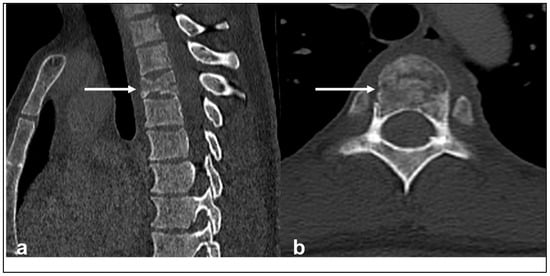

| Chondrosarcoma | Lytic lesion. ‘Rings and arcs’ calcification characteristic of chondroid matrix. | High T2 signal due to cartilage and myxoid content. Peripheral and septal enhancement. Enhancing extra-osseous soft tissue component. |